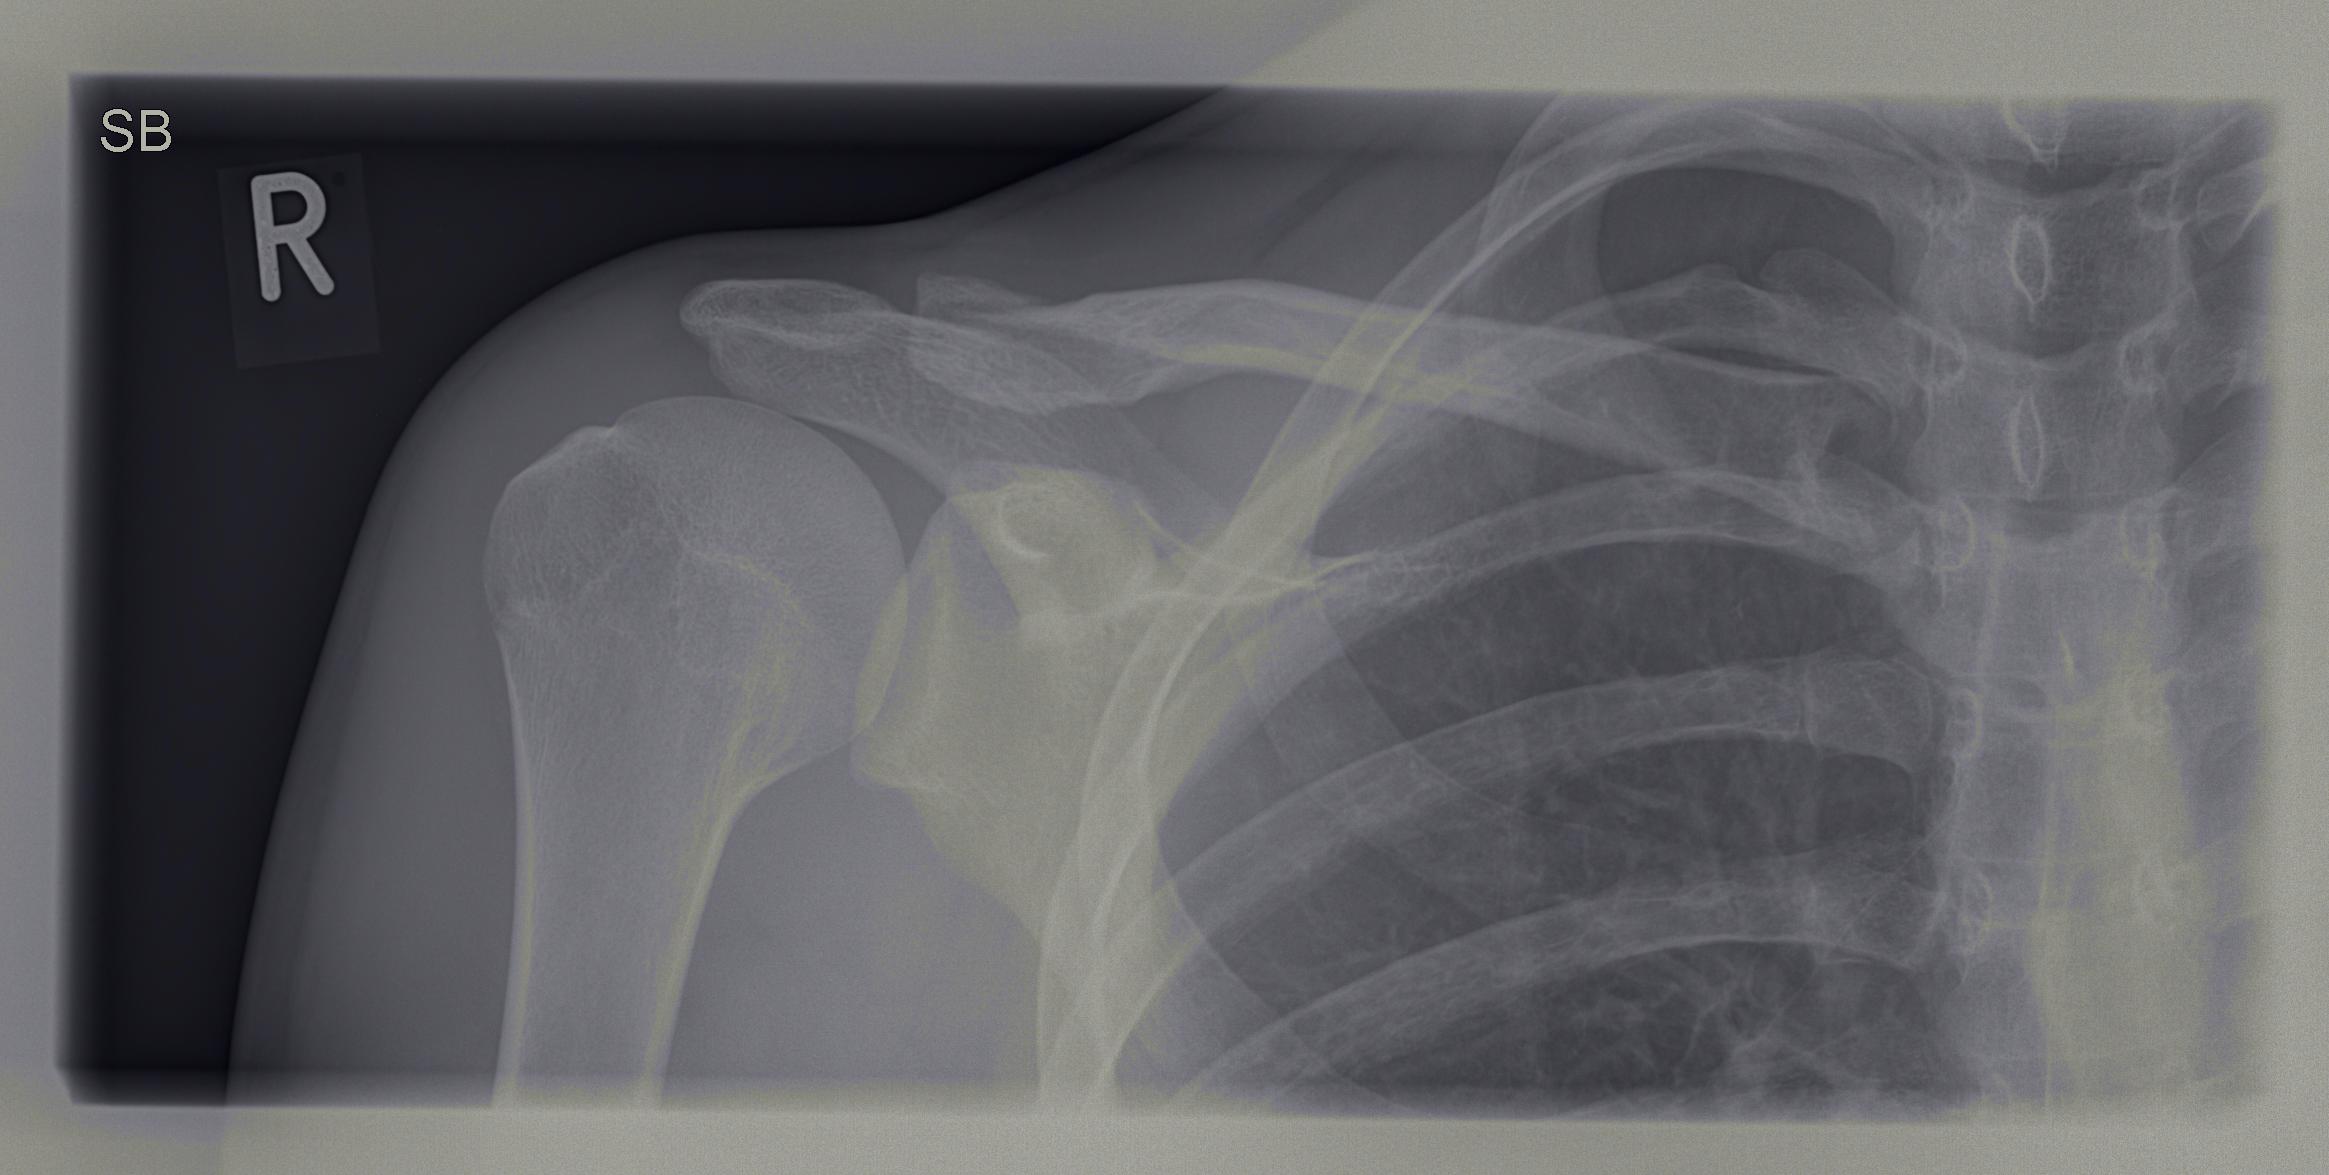

Schlüsselbeinbruch » Ursachen, Symptome & Behandlung

Schmerzen am Schlüsselbein einseitig Ursachen, Diagnose und effektive Behandlung

Die Schwellung, meist am oberen Rand des Brustbeins, wird Tietze Syndrom genannt. Es handelt sich um eine Entzündung des Rippen / Brustbeingelenks und ist deshalb leicht seitlich des Brustbeins zu finden. Häufig ist die erste Rippe betroffen, da hier zusätzlich zur Rippe auch das Schlüsselbein mit dem Brustbein verbunden ist.. Was können Ursachen sein, wenn das Schlüsselbein geschwollen ist? Geschwollene Lymphknoten am Schlüsselbein. Tietze Syndrom. Verletzungen des Knochens (Schlüsselbeinfraktur) Degeneration (Arthrose an den Schlüsselbeingelenken) Verletzung des Muskels (Muskelfaserrisses der Brust) Überlastung. Fehlbelastung. Schlüsselbeinbruch.